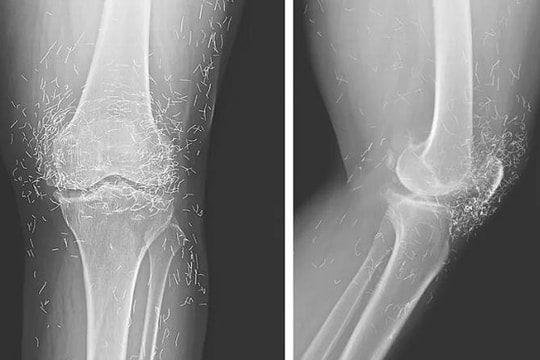

Chụp X-quang vài giây, bệnh viện phải 'treo' kết quả đủ 6 phút

Nghịch lý chụp X-quang vài giây, bệnh viện phải 'treo' kết quả đủ 6 phút

Máy móc hiện đại chụp X-quang trong tích tắc nhưng bệnh viện buộc phải "treo" kết quả cho đủ 6 phút mới gửi dữ liệu đi để tránh bị cơ quan bảo hiểm từ chối thanh toán.